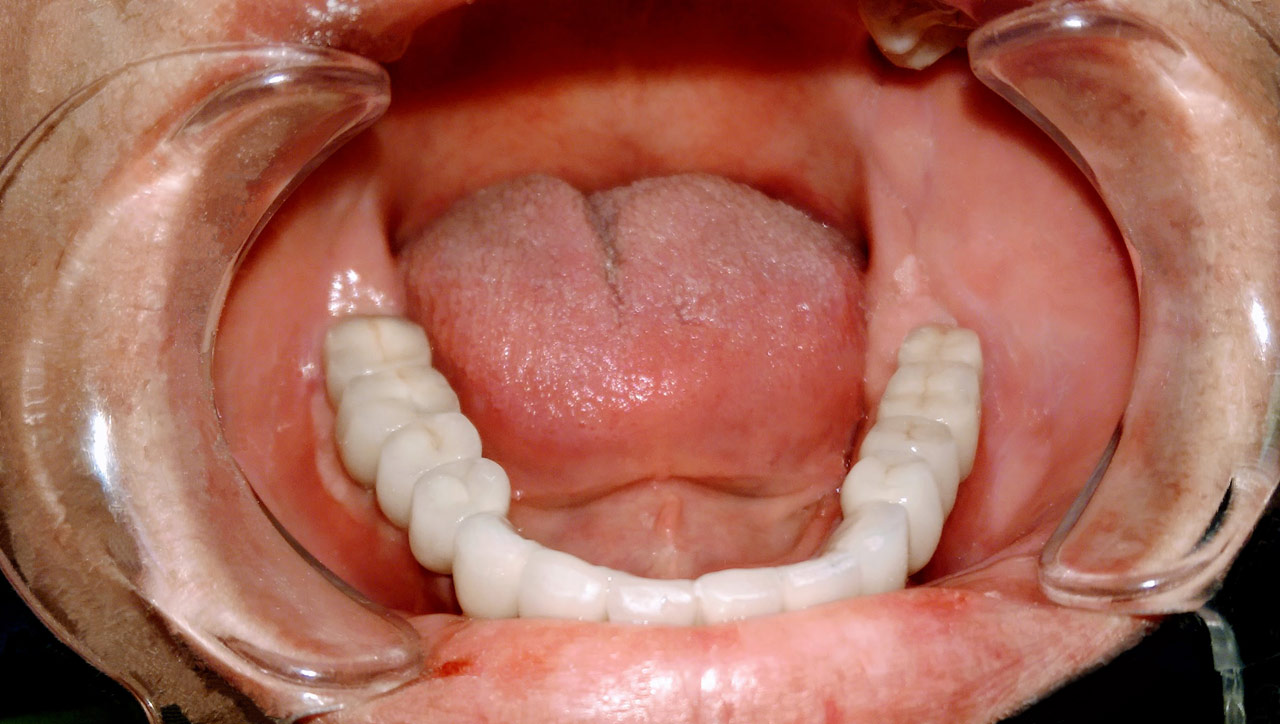

Teljes fogatlanság helyreállítása 2 nap alatt azonnal terhelhető svájci IHDE implantátumokkal és PMMA műanyag hidakkal. Intraorális szkennerrel vettünk lenyomatot az implantáció után, és erre a digitális mintára készítette el a fogtechnika a hidak digitális tervezését, majd faragta ki műanyagból. Ezt a gyors munkát az azonnal terhelhető implantátumok és a digitális lenyomat, tervezés segítségével tudtuk megcsinálni mindössze 2 nap alatt. Dr. Kelemen Péter és a Symbion Fogtechnika munkája.